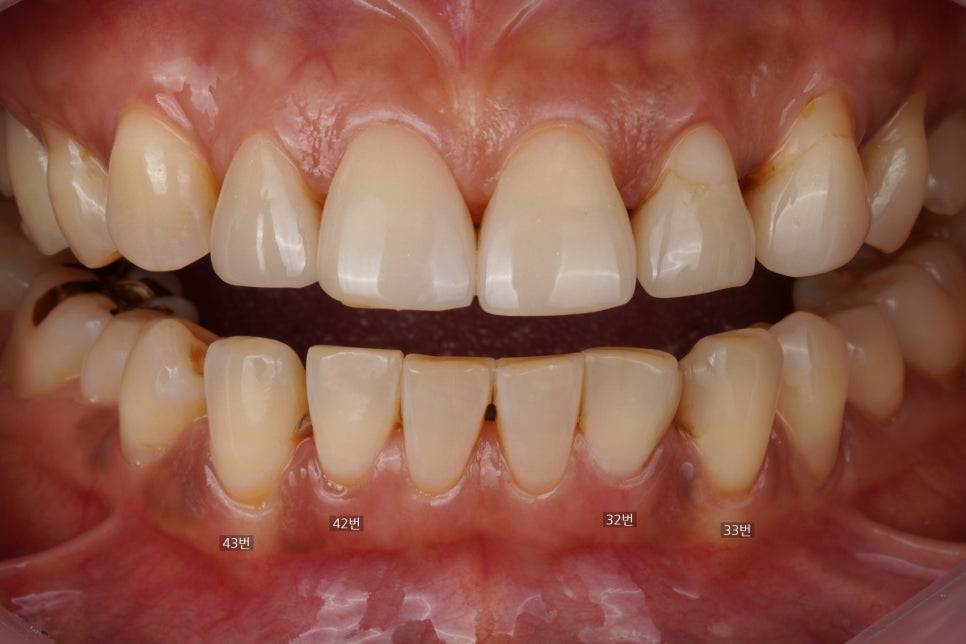

사진상 왼쪽 송곳니 부위

치석이 보이네요

위 사진에서 왼쪽 송곳니 부위(43번치아)에

기존에 치료했던 레진이 떨어지셨다고

말씀을 해주셔서 사진을 찍고

분석을 해보았습니다.

옛날 레진 (마모와 변색, 치석침착이 보입니다)

반대편 송곳니(33번치아)와 앞니(32번) 사이에도

예전에 때워놓은 레진 재료가 붙어있는데

왜냐면 사진에서 보시다시피

옛날 레진이 다 마모가 되어있고

그 주변으로 변색도 있고

레진 하방으로 치석도 많이 쌓여 있어서